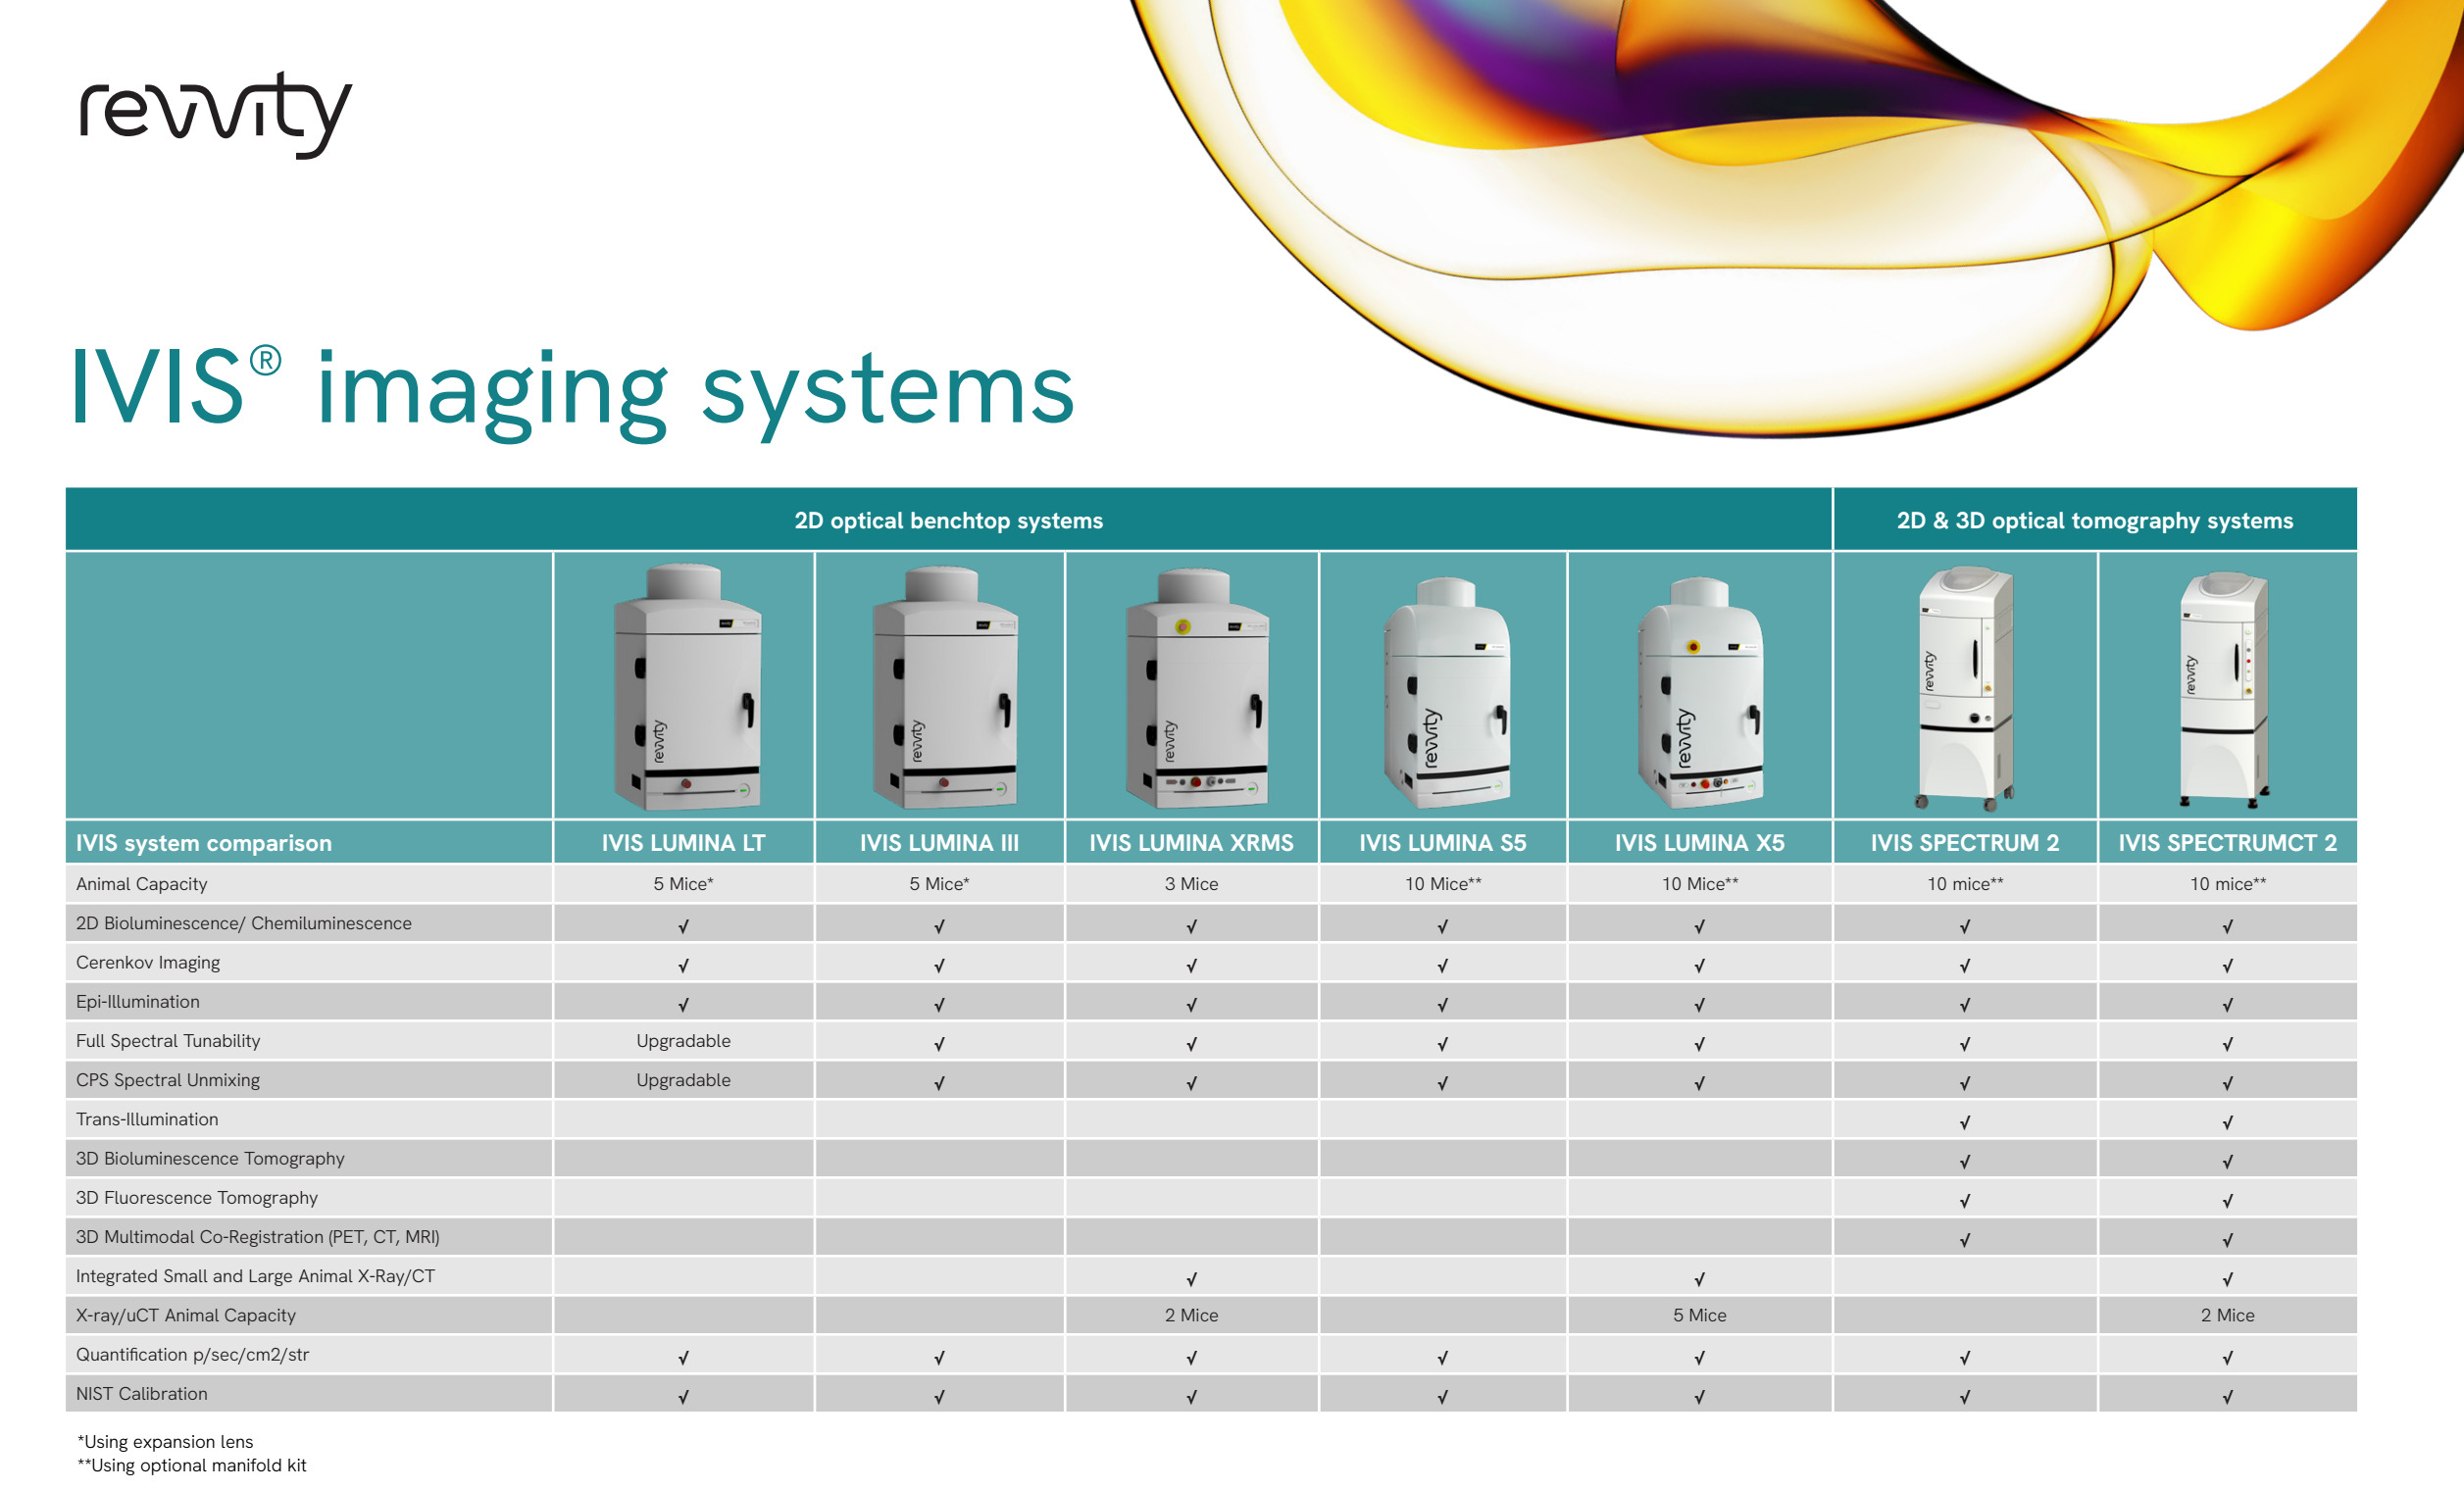

Porównanie aparatów IVIS EN